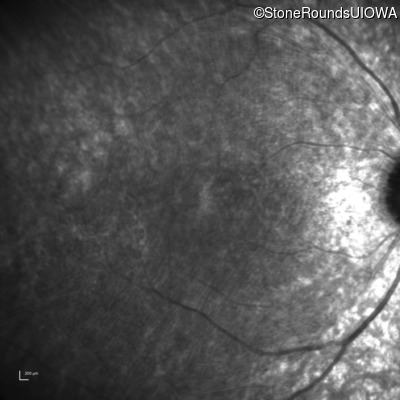

Age at visit: 7 years

This 7 year old boy's mother first noticed that he was tripping over objects in dim light about one year ago.

Diagnosis & molecular findings

Batten Disease PPT1 Thr75Pro ACC>CCC IVS6-1 G>T AR